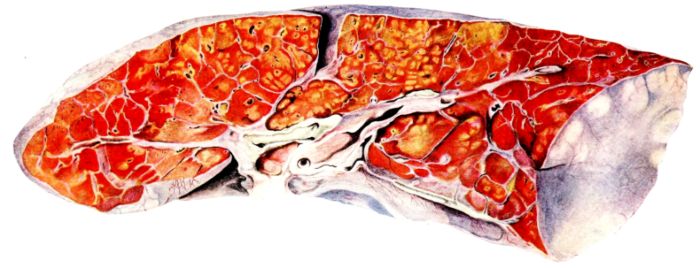

FIG. XIII. AUTOPSY NO. 96. RIGHT LUNG. A WATER COLOR DRAWING OF A GROSS LUNG IN THE ACUTE STAGE. NOTE THE SIZE OF THE LUNG, THE HEMORRHAGES ON THE PLEURAL SURFACE, AND THE BLUE AREAS OF CONSOLIDATION.

19The lungs are extremely voluminous (12, 17) due in part to an accumulation of liquid within them. This finds its way into the trachea and completely fills the latter structure with blood-stained, syrupy fluid, with purulent material, or with a mixture of these (2, 90, 107, 157, 162). At first the pleural surface is smooth and often quite even, but on closer inspection, a minute granulation is suggested. In many cases even close examination does not allow the conclusion that an exudation of anything but serum has occurred through this membrane, except in localized foci. These foci more frequently involve the interlobar pleura and that of the lower lobes (112, 143). The volume of the lungs, often great enough to obliterate the pericardial area, is one of the two most characteristic features of the external examination. The other feature is their color. Small, bright red hemorrhages may occur anywhere. The larger patches are the most striking. Violet, purple, or dark brown areas, irregular in shape and distribution, are more frequently found on that portion of the pleura over the lower two-thirds of the lung. Between the deeply colored zones, there are pale pink areas which involve the lowermost edge to the least degree, the anterior margin somewhat more, and the apex of the lung most of all. The darker portions just referred to may project above the surface and may be circumscribed, resembling huge, fresh hemorrhagic infarcts (41, 108). The alveolar walls are not seen through the pleural surfaces in these darker zones. The pale pink areas, usually at the level of the more intensely colored zones, may be elevated and the dilated air sacs are distinctly made out through the pleura (Fig. XIII). At the hilum, the lymph glands are large and soft. When cut, fluid escapes and is often blood-stained. The cross section may present a distinct, diffuse, hemorrhagic appearance (162). At the hilus, too, the lymphatics, distended here and there over the surface of the pleura, are most affected. The congested bronchial mucous membrane and the exudate in these structures has been described.

After removal, the lung retains its shape, but is more flaccid than the consolidated lung of lobar pneumonia. It cuts with very little resistance and immediately a large amount of a syrupy, pink fluid escapes and obscures the entire area. With the fluid scraped away, the variations in the consistency of the lung become visible. The pale areas around the borders and chiefly at the apex in which the air sacs are discernible with the naked eye, sink slightly below the remainder of the surface, and the pleural edge inverts. The individual lobules of the lung in these areas are more conspicuous than normal, because the interstitial tissue bearing the lymphatics and vessels, as well as that around the bronchi and larger blood vessels, does not lose its edematous appearance as quickly as the alveoli (40, 92, 110, 164), and, consequently, these grey lines and points stand up somewhat more prominently.[6] In contrast with the paler areas which are prone to slight collapse, the remainder of the cross section retains its more smooth and even surface. The alveolar walls are not distinctly made out, but the terminal bronchioles often make themselves evident by the nature of the material which is within and by their distinct dilatation (1, 67, 110, 149, 162). The more firm areas stand out, too, on account of their difference in color. The scheme is not unlike that seen on the pleural surface, and while dark, almost black, infarct-like areas occur on the cut surface, the solid areas are more likely to be translucent, dull, light red, brown or even grey. They have a surface similar to a very fresh, tuberculous, gelatinous pneumonia, but the color differs from the cloudy grey of the latter on account of the admixture of blood in the exudate and the great congestion of the vessels (Fig. XIV).

The well developed post-mortem muscular rigidity, the lividity of the dependent parts, of the face with its mucous membranes, and often of the trunk, the jaundice variable in extent, the crusts of blood on the nares and mouth, and the splanchnic dilatation are features which prepare for the gross picture presented by the thoracic organs. The increased moisture within the pleural cavities associated with the even, translucent pleural surface, whose dilated lymphatics become more and more prominent towards the hilum, the large succulent lymph glands, and the exudate in the bronchial tree, are all striking, but more characteristic of the gross picture, is the great increase in volume of the lung itself, mottled 20with brilliant colors. The lung, too, is very wet and on section, after the syrupy, blood-stained fluid escapes from the less definitely consolidated zones, the latter appear, not as the usual granular, firm areas of hepatization, but have more the consistency of a gel, and also its translucence. Characteristic of this disease as these changes may be, the specificity of the fundamental lesion in the respiratory tract, becomes more emphatic after study of its histology (92, 162).